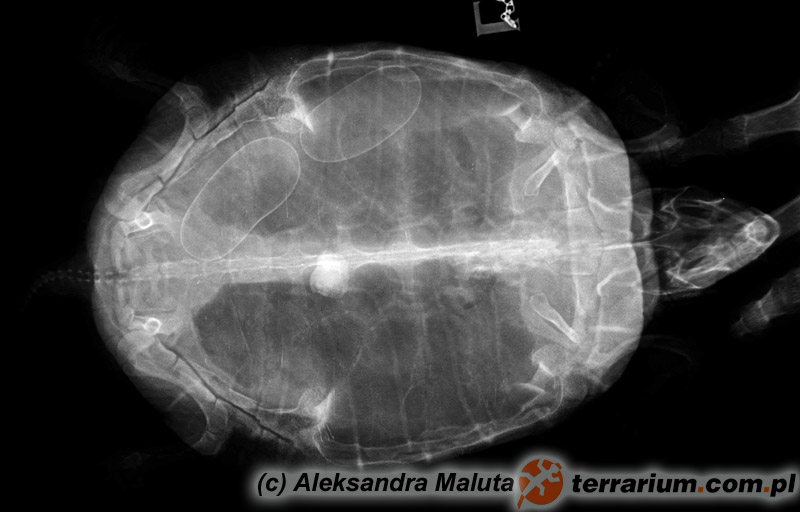

Żółwie to jedni z trudniejszych pacjentów, jeśli chodzi o diagnostykę. Obecność pancerza znacznie utrudnia badanie przez tzw. omacywanie, czyli palpację. Często potrzebne są badania dodatkowe, takie jak zdjęcie RTG, czy USG. Niestety w przypadku pierwszych, częstym problemem jest interpretacja wyniku, nawet specjaliści radiolodzy, opisujący RTG u psów i kotów mają kłopot z prawidłowym opisem badań wykonanych u żółwi, ze względu na ich szczególną anatomię. W obrazie RTG cień pancerza zaciera obraz narządów wewnętrznych i tylko osoba mająca doświadczenie w interpretacji obrazów rentgenowskich gadów i znająca ich anatomię może się pokusić o opis prześwietlenia, na którym brak ewidentnych zmian takich jak np. uwapnione jaja, bądź cieniujące ciało obce np. kamień.

W takiej sytuacji koniecznie należy wykonać zdjęcie RTG, a najlepiej dwa – w dwóch projekcjach, żeby dokładniej określić umiejscowienie ciała obcego oraz wypełnienie przewodu pokarmowego. Jeśli w badaniu rentgenowskim zostanie potwierdzona obecność ciała obcego (podobne objawy mogą dawać silne inwazje pasożytnicze), gadzina zazwyczaj jest kwalifikowana do operacji. Przed operacją powinny być wykonane badania biochemiczne krwi, aby dobrać odpowiednią do stanu pacjenta – najbezpieczniejszą narkozę. Podobne postępowanie diagnostyczne przeprowadza się w przypadku zaparcia jaj u żółwic. Pamiętajcie! Podanie oxytocyny, bez wcześniejszego zdjęcia rentgenowskiego określającego ilość jaj, ich wielkość, położenie oraz stan skorup, może przynieść więcej szkody niż pożytku. Nierzadko zdarza się, że jaja, które są zbyt duże i utknęły w kanale miednicznym, po podaniu hormonów cofają się… do pęcherza moczowego! A usunięcie ich z niego to prawdziwe wyzwanie i zegarmistrzowska robota.